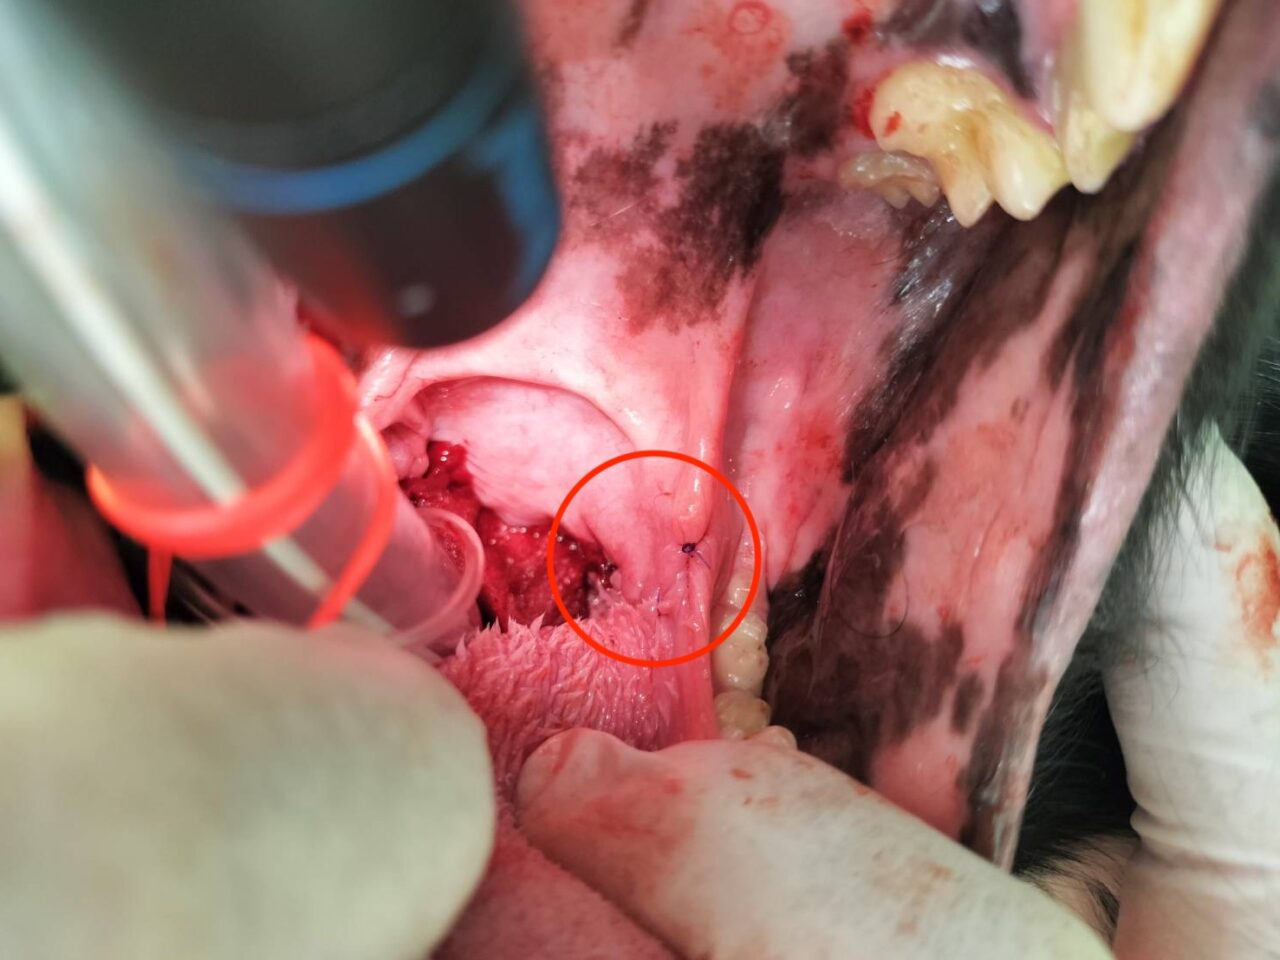

以下、扁桃の写真となります。苦手な方はご注意ください。

左側の扁桃が腫れています(赤丸)。

扁桃を切除し、縫合後(赤丸)。